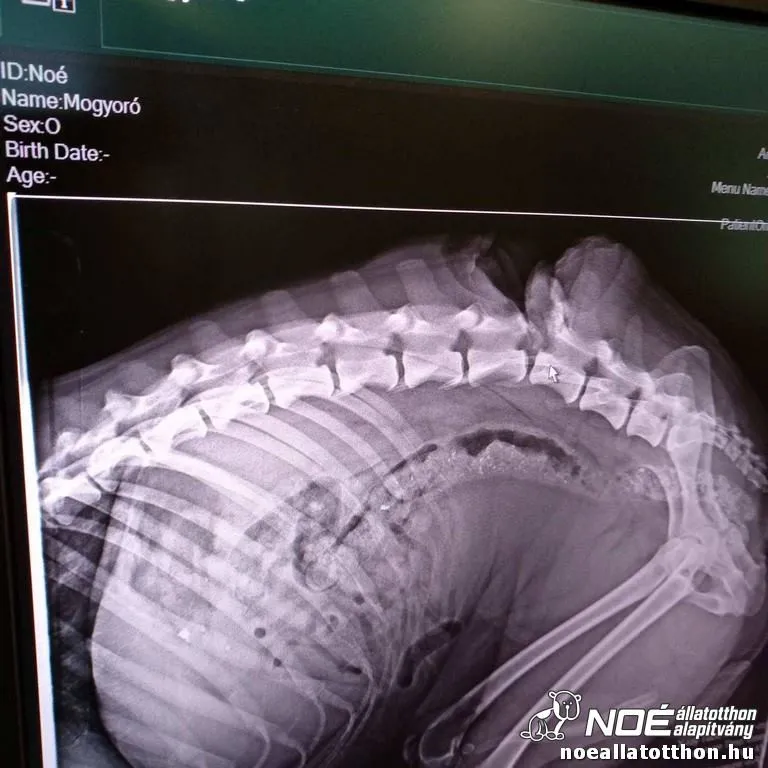

Gólya lépked kutyaház előttSüni állatorvosi asztalonZöld, sárga és szürke mintázatú kaméleon emberi kézenNégy képes montázs a Noé új létesítményeoről: piros, fedett padok a cicakifutóban, Kisgazdasági udvar, kék sátorépület és járda betonozásaKét kis kecskegida emberi kézbenNégy képes montázs a Noé új állatszállító autójáról, Köszönjük! felirattalHárom képes montázs védőgallérban gyógyuló kutyáról és törött lábáról készült röntgenfelvételről műtét előtt és utánSzomorú, gipszelt lábú kutya lábadozik rácsok mögöttHárom képes montázs állatorvosi asztalon fekvő kutyáról és töréseiről készült röntgenfelvételrőlNégy képes montázs szembetegségtől szenvedő kutyáról műtétje előtt, közben és utánRöntgenfelvétel kutya gerincsérülésérőlBőrbeteg, félig csupsz, félig hosszú, összefilcesedett csimbókokat viselő kutya állatorvosnálPici, fejlődési rendellenességgel született francia bulldog kölyök ölbenÚjszülött, nedves szőrzetű kölyökmacskaCsontsovány, legyengült boxer kuporgó helyzetben állatorvosnálCsontsovány francia bulldog állatorvosnálLebénult hátsó felű francia bulldogBőrbeteg, szomorú francia bulldogErősen deformált lábú kutyakölyök állatorvosi mérlegenSzaporítótelepről mentett kölyökkutyák autó rakterében, kartondobozokbanVilágoskék szemű kutya nyakába nőtt lánccal, narancs méretű kinővéssel állatorvosi vizsgálat közben